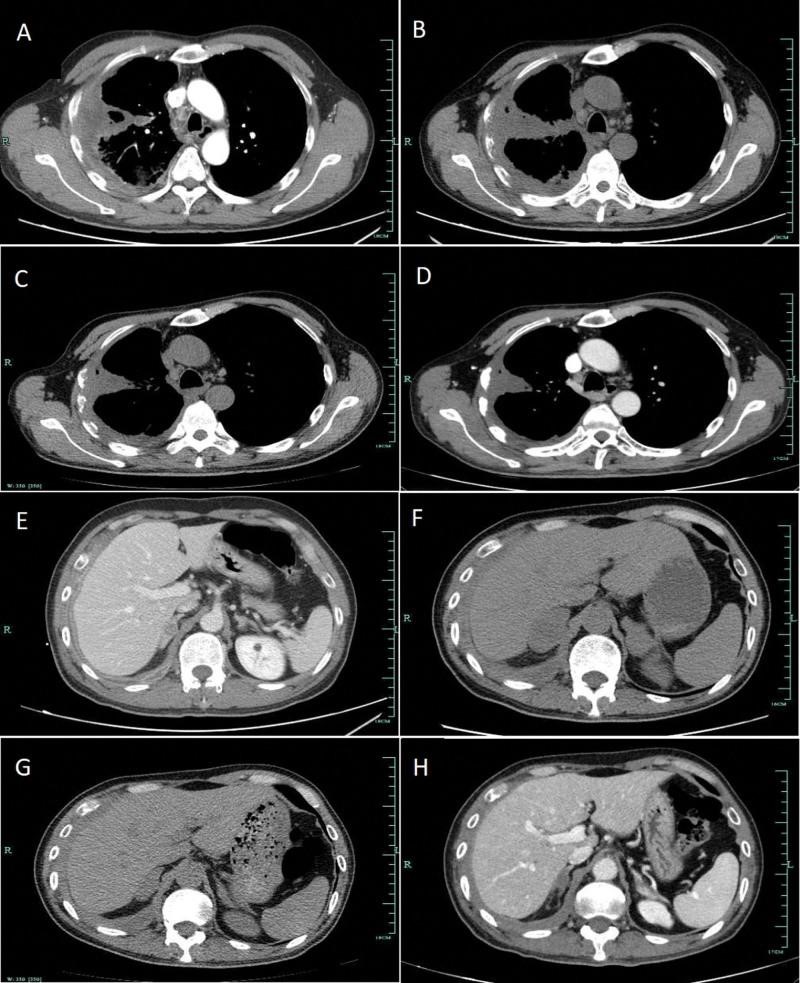

埃克替尼于2019年11月12日作为一线靶向治疗给药。此外,患者接受了右侧肩胛骨的姑息性放疗。两个月后,胸部CT显示肺部肿块无明显变化,胸膜增厚,淋巴结肿大,但双侧肾上腺转移灶有明显进展。采用患者血浆进行了包括9个基因的下一代测序基因测试,以排除共存基因突变。结果证实EGFR外显子19缺失是唯一的基因突变,丰度分数为2.06%。经过2个月的靶向治疗,患者出现严重疲劳,体重减轻4公斤。然后肺癌靶向用药指导基因检测选择 pembrolizumab 单药治疗作为二线治疗,剂量为每 3 周 100 mg。服用 1 剂派姆单抗后,患者随后又接受了 4 个周期的派姆单抗治疗。根据实体瘤反应评估标准1.1版,胸部和肾上腺的病变显著减少,导致部分缓解(PR)(图3)。然而,经过 5 个周期的免疫检查点治疗后,他的腿上出现了以斑疹和丘疹为特征的皮疹,覆盖了不到 10% 的体表面积(图 4A)。根据国家综合癌症网络关于免疫检查点抑制剂相关毒性的指南,这被确定为 1 级,并在受影响的区域应用了局部类固醇。然而,他的皮肤状况继续恶化,一周后斑丘疹变得更加严重,并蔓延到他几乎所有的腿、背部和部分胸部(图 4B,C)。它现在覆盖了他身体的 30% 以上,因此被归类为 3 级。皮疹以 1 mg/kg/d 的剂量用强的松治疗。最初,皮疹略有减少,但即使剂量加倍,药物也很快变得无效。患者随后因皮疹到另一家医院接受中药治疗,ICI治疗暂停。皮疹得到控制后,他接受了 4 个周期的紫杉醇(白蛋白结合)加顺铂化疗。2020年12月出现肝转移后再次采集血浆进行基因检测,结果仍显示除EGFR外显子19缺失突变(丰度为0.27%)外无其他致癌改变。然后,医生为他使用了埃克替尼加安罗替尼(一种口服小分子酪氨酸激酶抑制剂 VEGFR、PDGFR、FGFR、c-Kit 和 Met)。迄今为止,他已经服用了十一个月的联合靶向药物。该患者的治疗时间表如图所示图5.

图 3:EGFR-TKI 和 pembrolizumab 单药治疗期间 CT 上肺部 (AD) 和双侧肾上腺 (EH) 病变的变化。A/E:预处理。B/F:EGFR-TKI靶向治疗2个月。C/G:派姆单抗单药治疗 1 个周期。D/H:派姆单抗单药治疗 5 个周期。